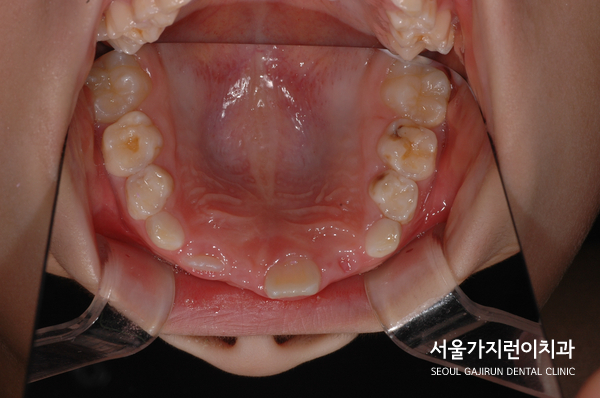

해당 환자분의 경우 8세의 남아였는데요. 앞니가 180도로 돌아간 상태로 매복된 것을 확인할 수 있었습니다. 거꾸로 숨어있던 건데요. 매복된 치아의 견인을 위해 치아에 버튼을 달고 치근 흡수를 조심하면서 아주 약한 힘으로 견인치료를 진행했습니다.

다행히 치료를 시작한 지 14개월 만에 앞니가 형태를 보이고 자리를 잡아갔는데요. 이 케이스의 경우 비교적 일찍 치아교정을 시작했다는 전제조건이 있었는데요. 매복된 치아가 잇몸뼈와 심하게 유착이 되었다면 교정력을 아무리 주어도 치아가 내려오지 않을 가능성이 있었습니다. 그렇기 때문에 상악 중절치의 매복을 비롯한 치아 맹출 장애는 치아교정전문치과에서 진료를 받아야 하는데요.